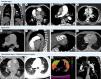

CTEPH should also be suspected at the time of acute PE when CTPA shows findings suggestive of chronic fibrothrombotic deposits – bands, webs, arterial narrowing or retraction, and/or dilated bronchial arteries (Figure 5) – or when the echocardiogram depicts an estimated PASP >60 mmHg and/or features of RV dysfunction and hypertrophy.14 In asymptomatic patients with risk factors (Figure 1) or a high CTEPH prediction score (Table 1),20 diagnostic assessment should also be considered.2 A proposed diagnostic algorithm is shown in Figure 6. Initial assessment of patients with suspected CTEPH should include a transthoracic echocardiogram to determine the probability of PH (Table 2) and a V/Q scan to look for mismatch perfusion defects.2 In general, especially considering that CTPA performed by chest radiologists is not widely accessible, a V/Q scan remains the gold standard exam for exclusion of CTEPD without PH at rest, due to its high sensitivity (96.2–97.4%) and negative predictive value of almost 100%47,48 (Figure 7). Other perfusion techniques, such as dual-energy CT scan or magnetic resonance perfusion, may be superior to a V/Q scan (Figure 8). However, these are more technically challenging and expensive, have limited availability, and lack multicenter validation.3

Computed tomography pulmonary angiography findings in chronic thromboembolic pulmonary hypertension. (A) Coronal image showing fibrothrombotic retraction with partial obstruction (yellow arrow) and eccentrically located thrombus with a broad base forming obtuse angles with the vessel wall, due to incomplete thrombus resolution (blue arrow); (B) axial image with intravascular webs (purple arrows); (C) axial image with total left PA occlusion (red arrow) and segmental arterial retraction (orange arrow); (D) calcifications within fibrothrombotic deposits in the right PA, illustrating the chronic component of the disease (green arrows); (E) axial image depicting main PA dilatation (double-headed arrow); (F) sagittal image showing RV outflow tract hypertrophy (double-headed arrow); (G) cardiac short-axis image with flattening of the interventricular septum (black arrows) and D-shaped left ventricle; (H) axial image showing segmental artery-to-bronchus diameter ratio of >1:1 (arrowheads), flattening of the interventricular septum, RV hypertrophy and RV/LV diameter ratio >1 (double-headed arrow); (I) peripheral nodular opacity (brown arrow) in the right upper lobe secondary to previous pulmonary infarction along with intra-arterial fibrothrombotic deposits (blue arrows); (J) axial image showing sharply demarcated segmental and subsegmental areas of hypo- and hyperattenuation (dotted lines); (K) (same patient as in panel J) color maps showing the distribution of perfusion: spectrum from green to red indicates increasing perfusion (hypoperfusion indicated by green areas); (L) sagittal image with bronchial artery hypertrophy (blue arrows). LV: left ventricular; PA: pulmonary artery; RV: right ventricular.